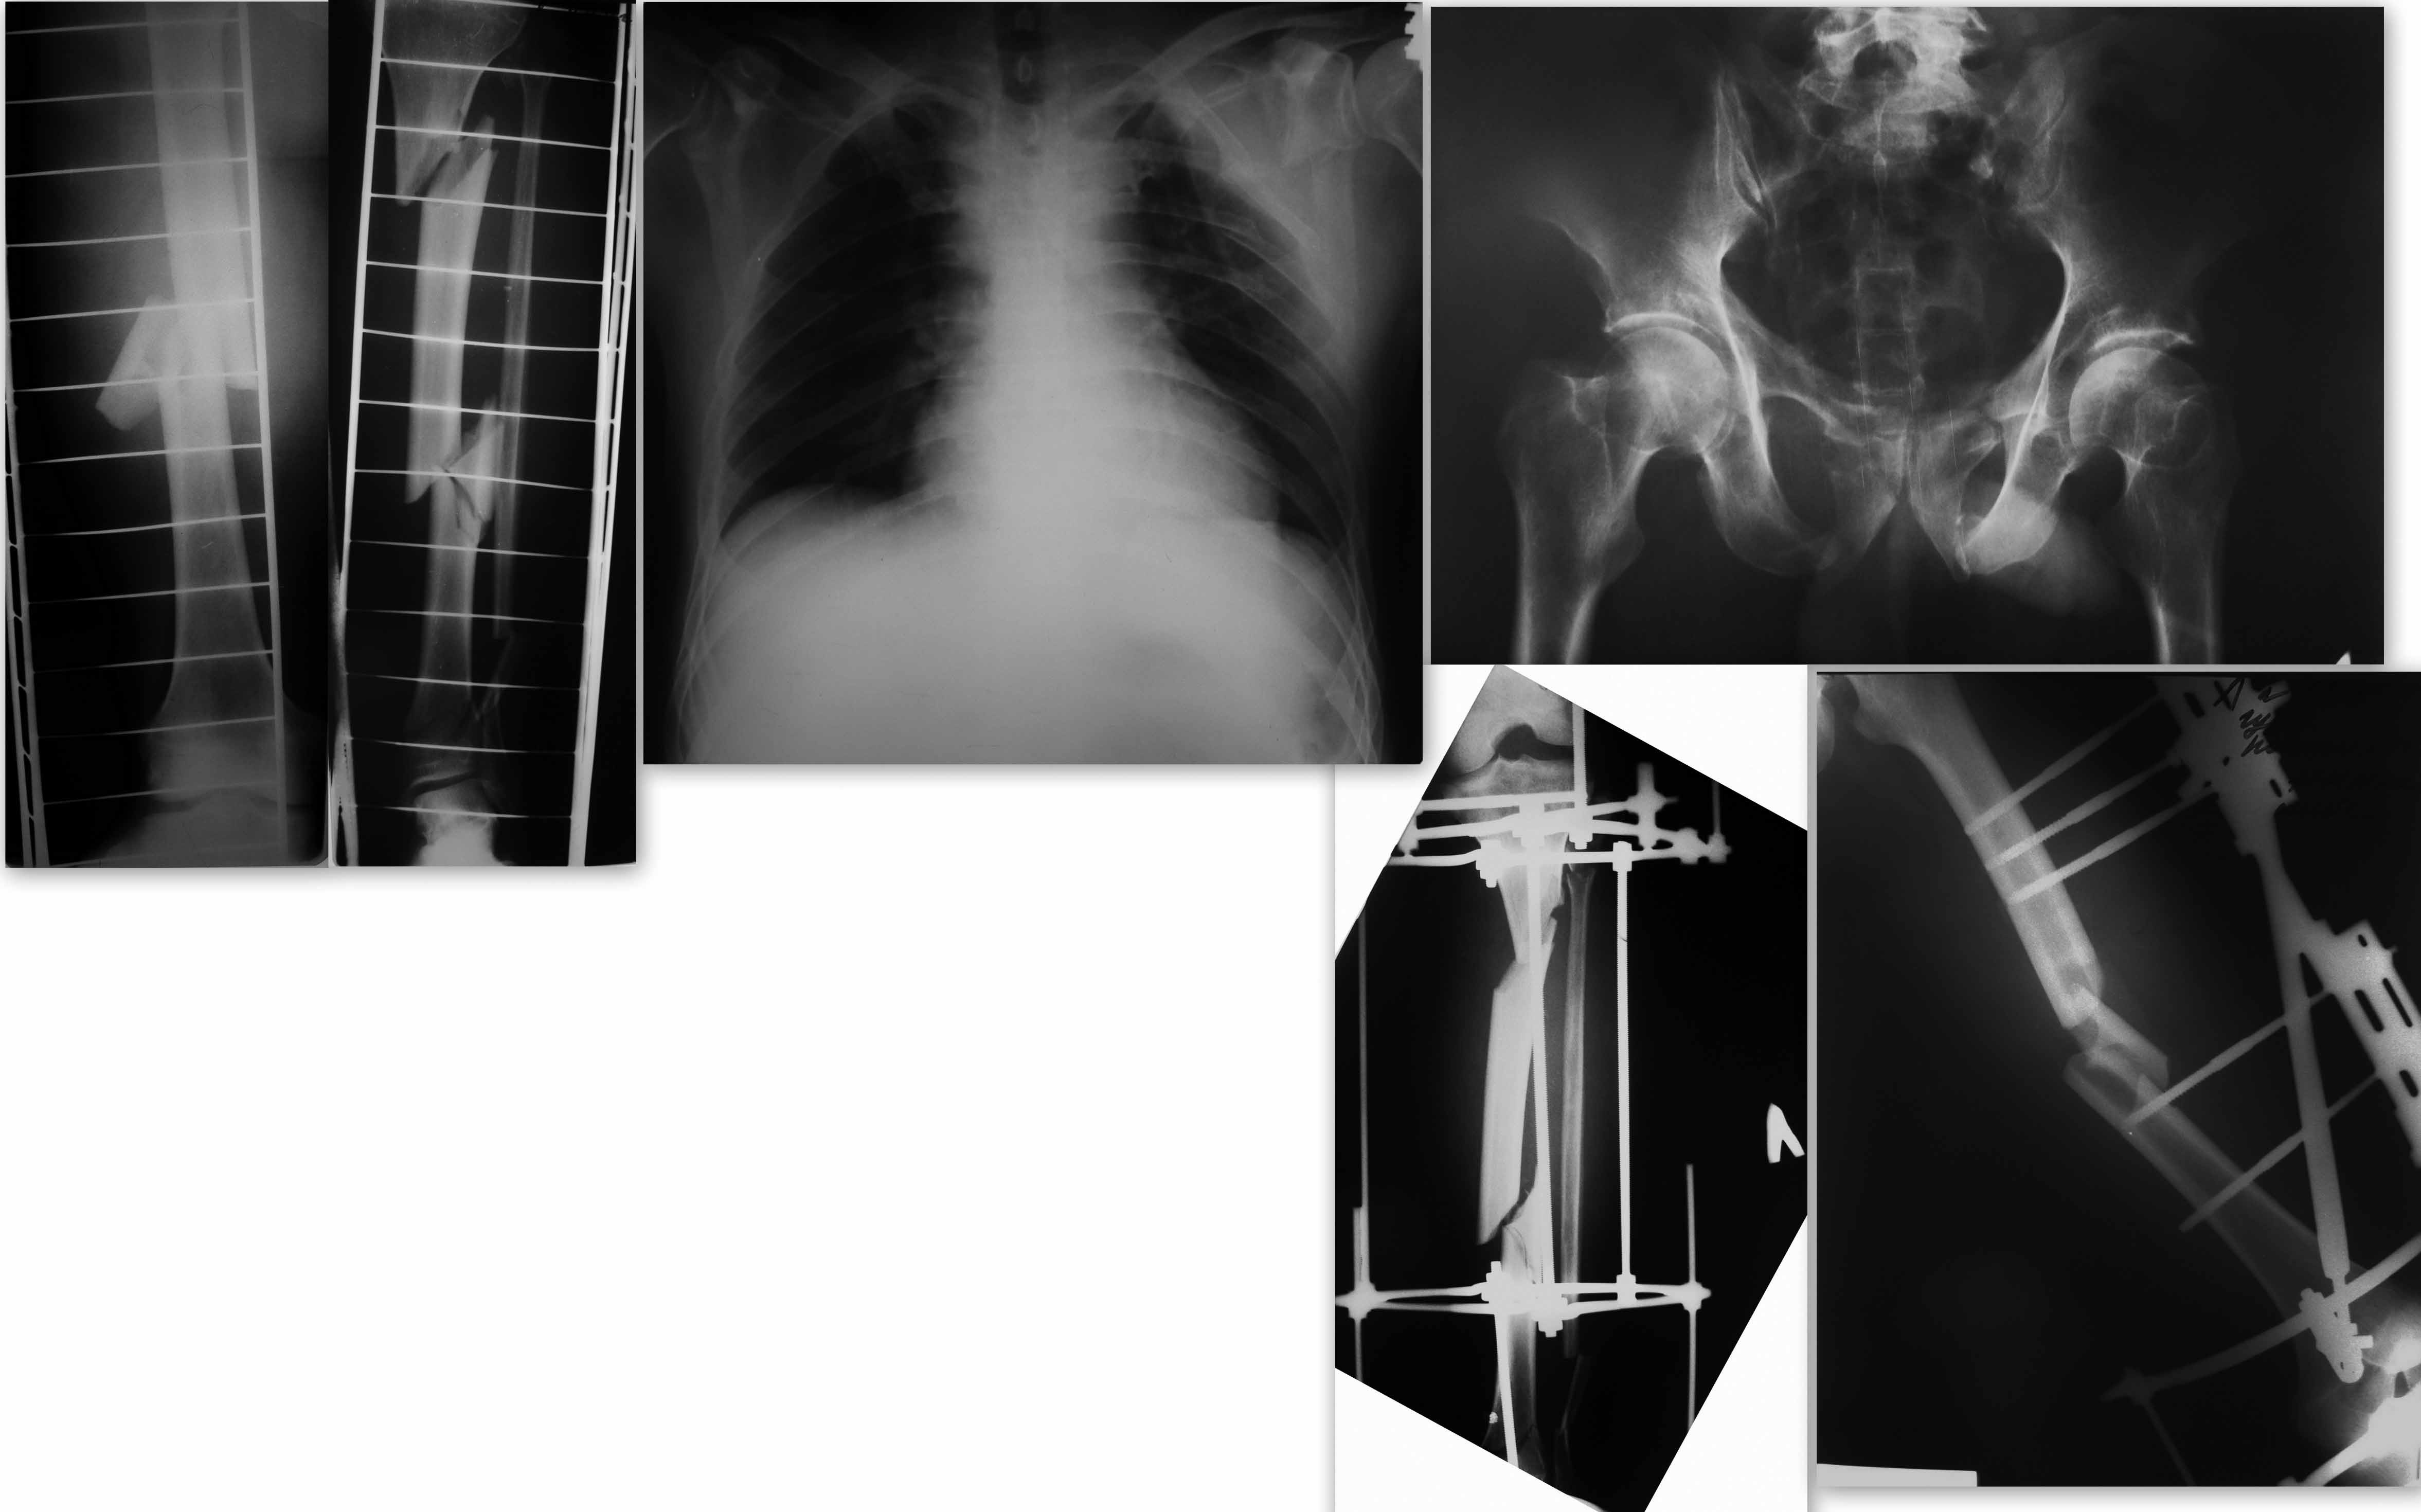

Со стороны таза, помимо переломов лонных седалищных костей, перелом боковой массы крестца слева; повреждение таза ротационно-нестабильное (B)и тоже требует фиксации, (учитывая гемодинамическую нестабильность при поступлении фиксировать таз необходимо было при поступлении)

по другим повреждениям: бедренная кость - БИОС, если есть проблемы с ранами области стояния чрескостных элементов, возможно с АБ покрытием.

Большеберцовая кость - может в этом случае есть смысл скомбинировать - пластина на дистальный отдел (после КТ(?); диафизарные переломы синтезировать стержнем.Вероятно потребуется и фиксация малобецовой кости.

Спасибо большое за комментарии. Я рад, что форум быстро откликнулся на сообщение. Дело в том, что больной уже прооперирован 29.11.11. очень экстравагантным способом в нашей клинике. оперировал "гуру", поэтому я от комментариев воздержусь. Выкладываю рентгенограммы на ваш суд.

Направление мысли было вполне приемлемое, а получилось кривовато, надо бы переделать.

Чудовищно! Все чудовищно! Начиная от объема и качества оказания помощи при поступлении, длительности обследования и качества обследования до времени операции, не говоря уже о самой "фиксации"....То, что при тяжелой политравме должно делаться в течении часа-двух, ну трех -четырех при плохой организации, растянулось на 4 дня... лучшее время для реконструкций с 5-6-го по 7-10 день после травмы

С 10 по 21 день лучше вообще не делать больших операций - большой процент нагноений, так как иммунитет угнетен (истощен).. Пациент оперирован на 18 день.... Намучается еще бедняга, особенно с голенью и тазом

Намучается еще бедняга, особенно с голенью и тазом

... и с левой лопаткой. Похоже, что перелом шейки лопатки со смещением.

Тоже нуждается в операции.

3. Б/б ?? Как делали? (открыто-закрыто) покажите снимки в живую! По поводу ротации не буду коментировать. КРИК ДУШИ: так лучше АВФ?

+100500 Огромное спасибо за понимание Andrew. Вы меня полностью понимаете. Мне кажется всех деятелей которые все знают и умеют, необходимо принудительно посылать на АО курсы. Я являюсь на данный момент лечащим врачом данного пациента, и мне сейчас приходиться что-то решать. На этой неделе наконец-то будет выполнен синтез переднего полукольца. И попытка устранения деформации путем синтеза малоберцовой кости. Варус как мне кажется с помощью этого не устраниться.

По представленным снимкам четко я бы и не сказал за счет чего такая наружная ротация - не факт, что не из-за перелома бедра или вообще из-за перелома шейки бедра (которой ни на одном слайде не видно).

Может быть, я чего то не понимаю, но мне видится, что заштифтовать голень было бы довольно проблематично ( короткий дистальный отломок ) Плюс действительно непонятно откуда такая ротация? И главное, где там варус, когда там вальгус и на бедре и на голени ?